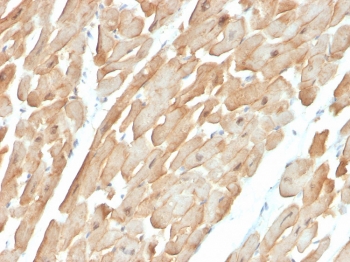

IHC staining of FFPE human cardiac muscle with Dystrophin antibody (clone DMD/3677). HIER: boil tissue sections in pH 9 10mM Tris with 1mM EDTA for 20 min and allow to cool before testing.